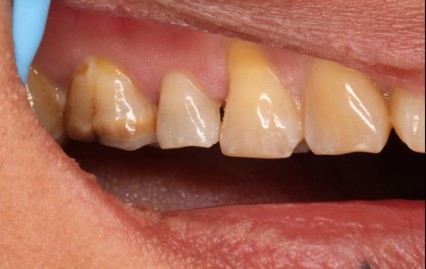

August 1, 2025: Tooth preparation, gingival retraction, shade selection, and impression taking were performed sequentially; the patient tolerated the procedures well